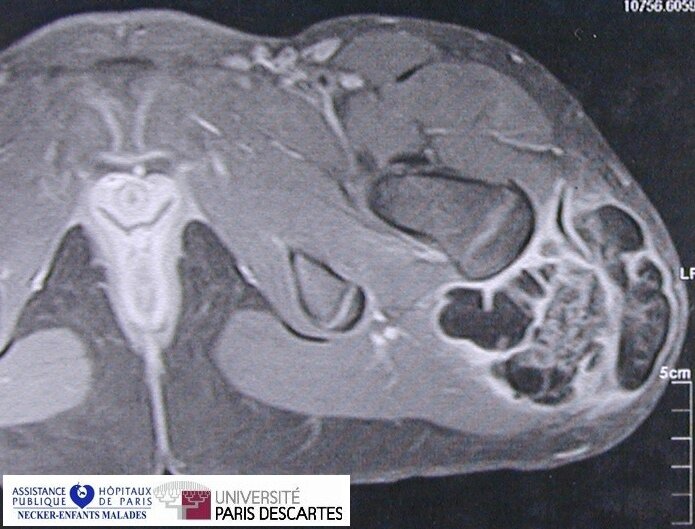

Tumoral Calcinosis